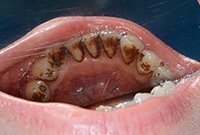

Удаление коричневого зубного налета

Профессиональная гигиена полости рта с целью удаления коричневого зубного налета у мужчины 37 лет.

Удаление коричневого зубного налета До

Удаление коричневого зубного налета После